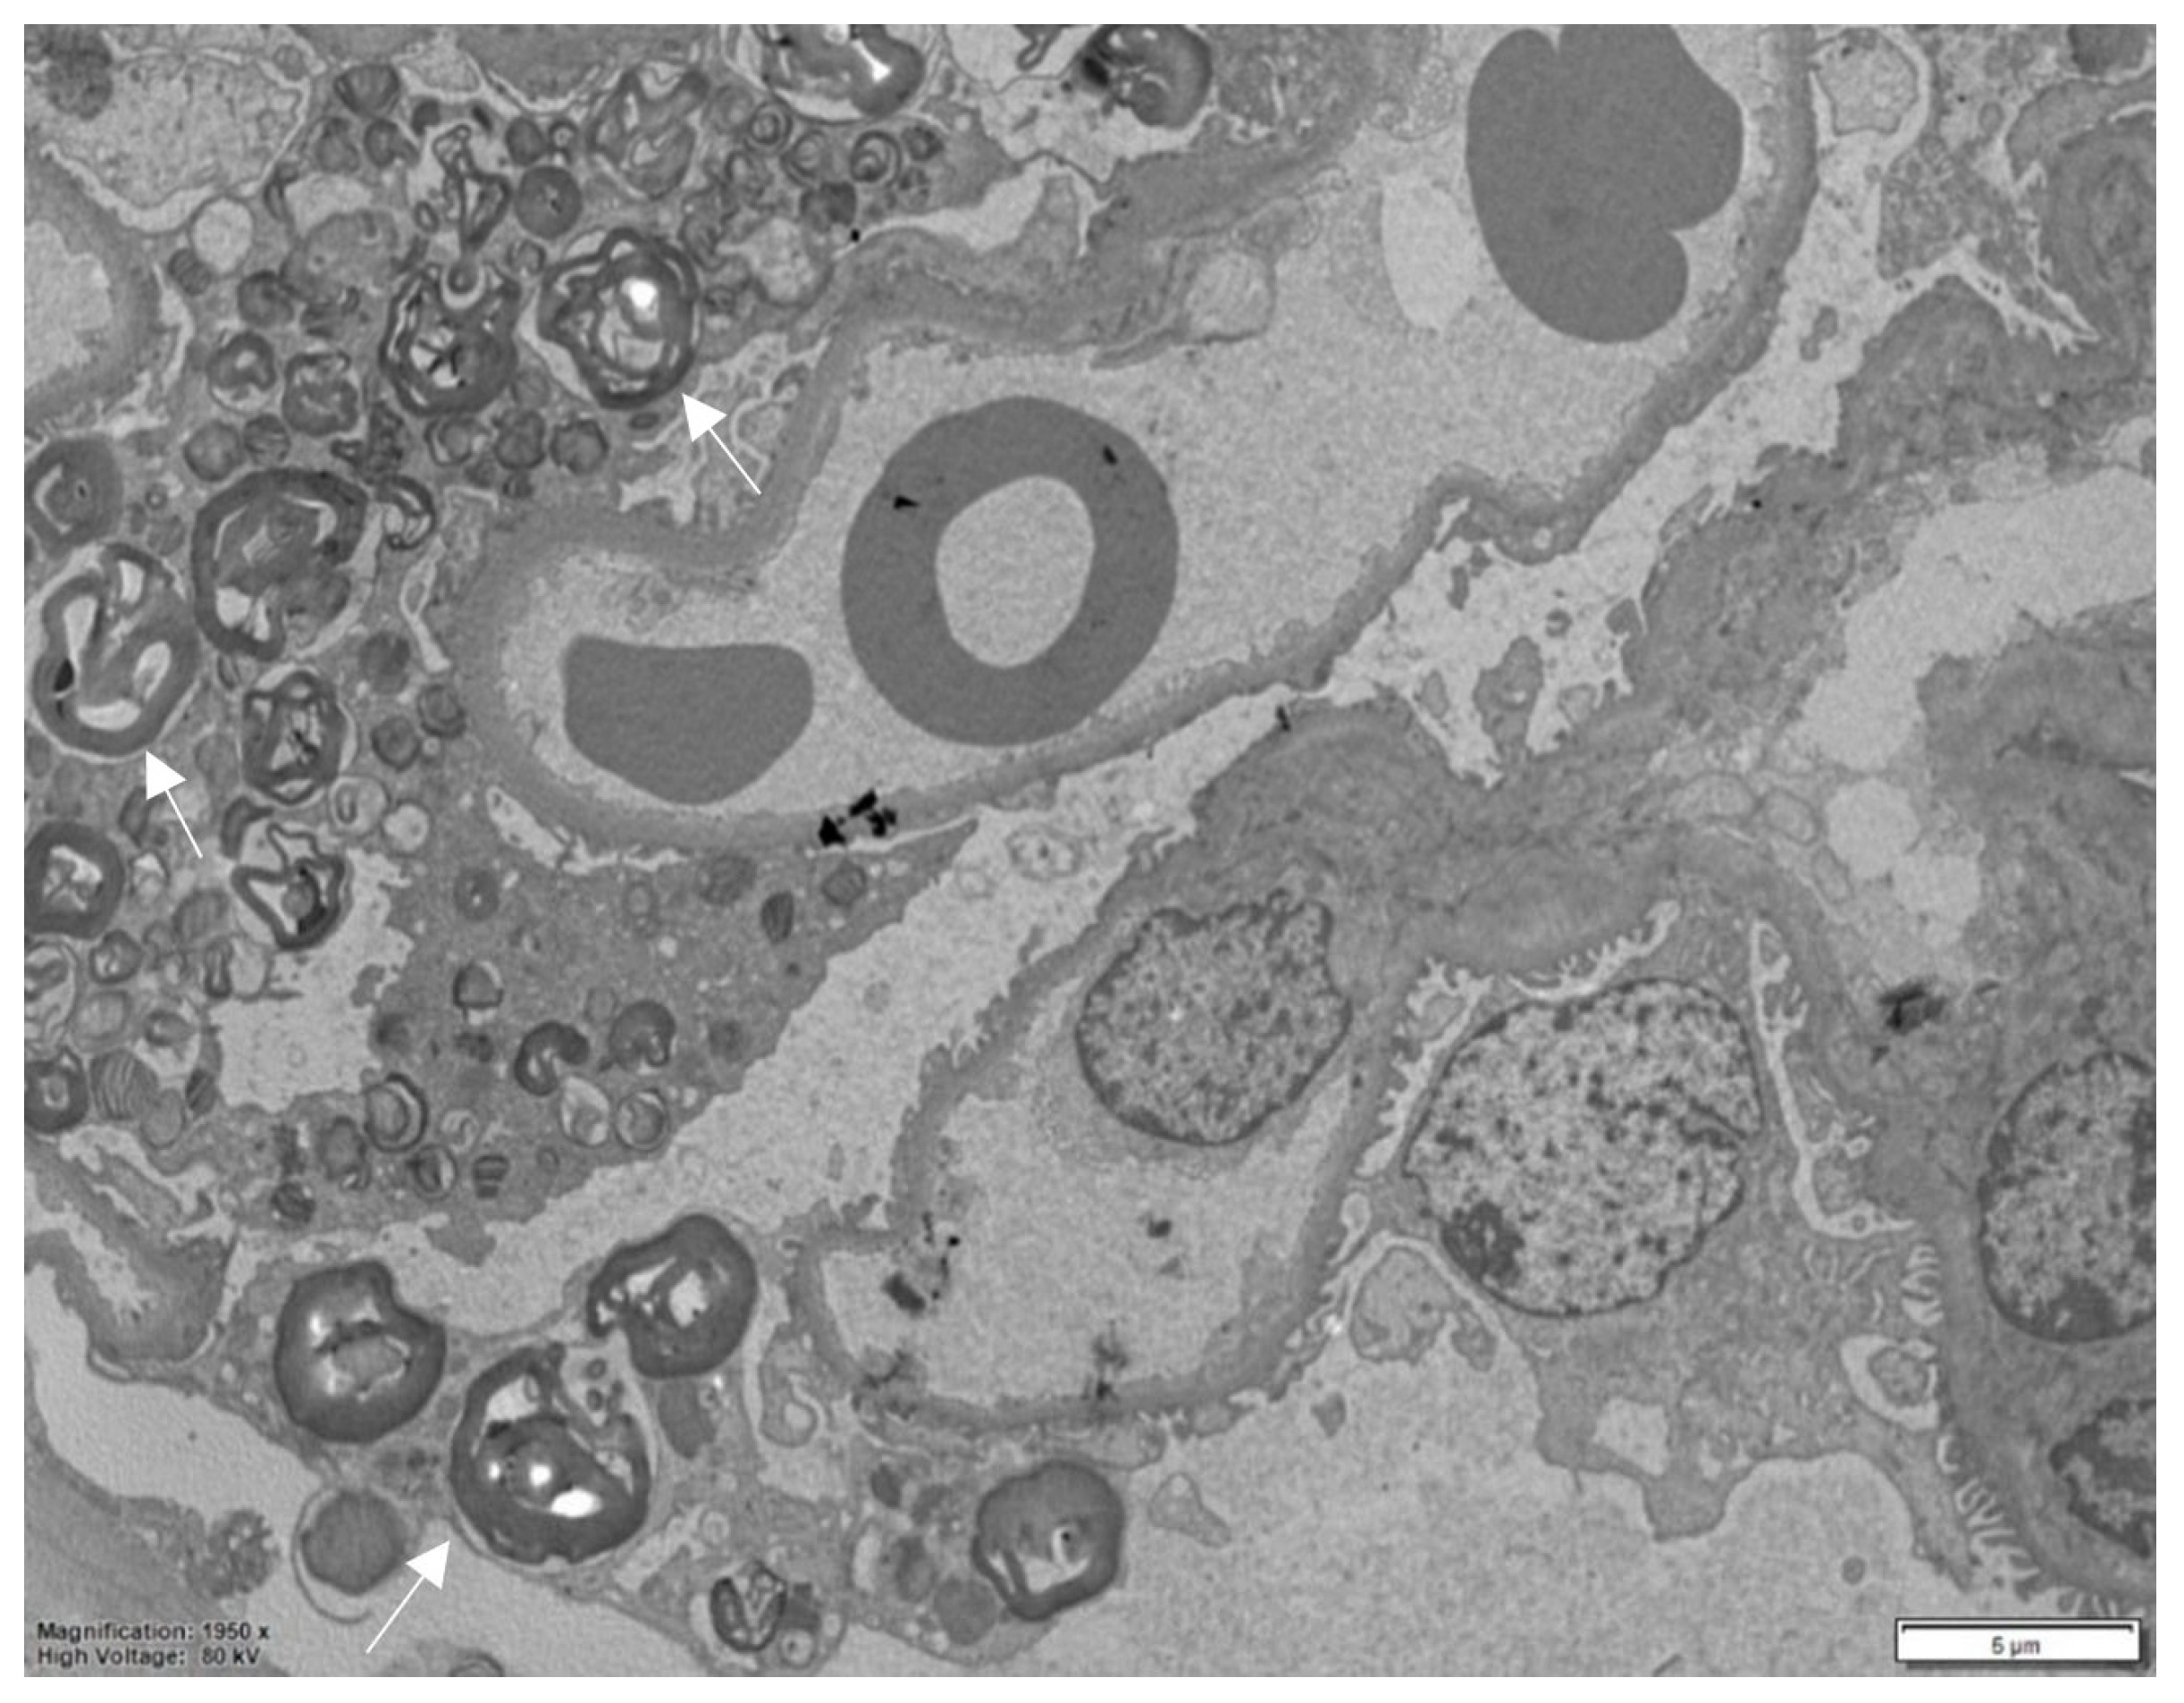

Electron microscopy, performed on plastic-embedded sections with a thickness of 60–80 nm, reveals that these deposits consist of lysosomes containing whorls of electron-dense lamellae alternating with electron-lucent spaces. This characteristic ultrastructural pattern is highly specific and aids in confirming the diagnosis.

Depending on the orientation of the cutting plane relative to the spatial configuration of the inclusion, digital images are produced that have been described by different observers as “myelin figures”, “onion skin”, or “zebra bodies” (Figure 3) [15,19]. It is noteworthy that in semithin sections stained with toluidine blue, Gb3 accumulation is clearly detectable in all kidney compartments, and this is considerably timesaving compared to ultrastructural studies (Figure 4).

Figure 3.

Electron microscopy, numerous myelin figures are observed within the podocyte cytoplasm in the glomerulus. The asterisk indicates an unaffected podocyte.